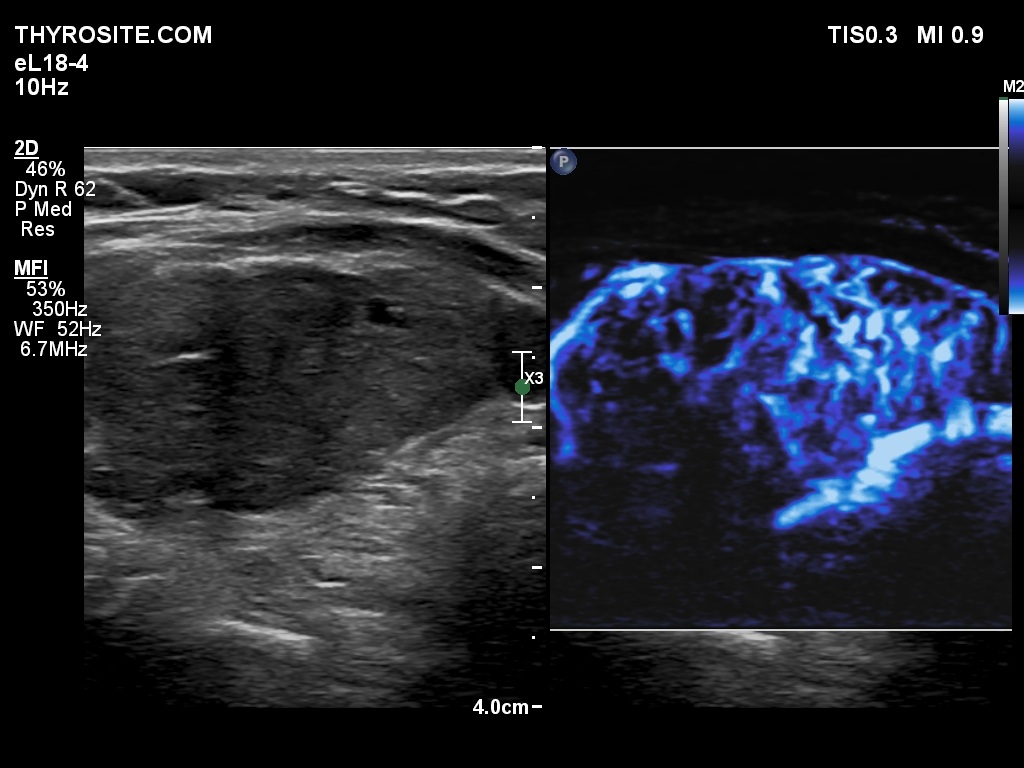

Right lobe, longitudinal scan

Left lobe, longitudinal scan, microflow imaging. The vascularization is increased.